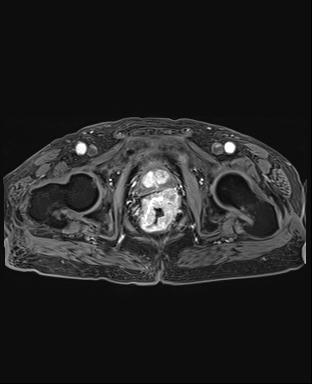

上圖為直腸癌術(shù)后復(fù)發(fā)患者。